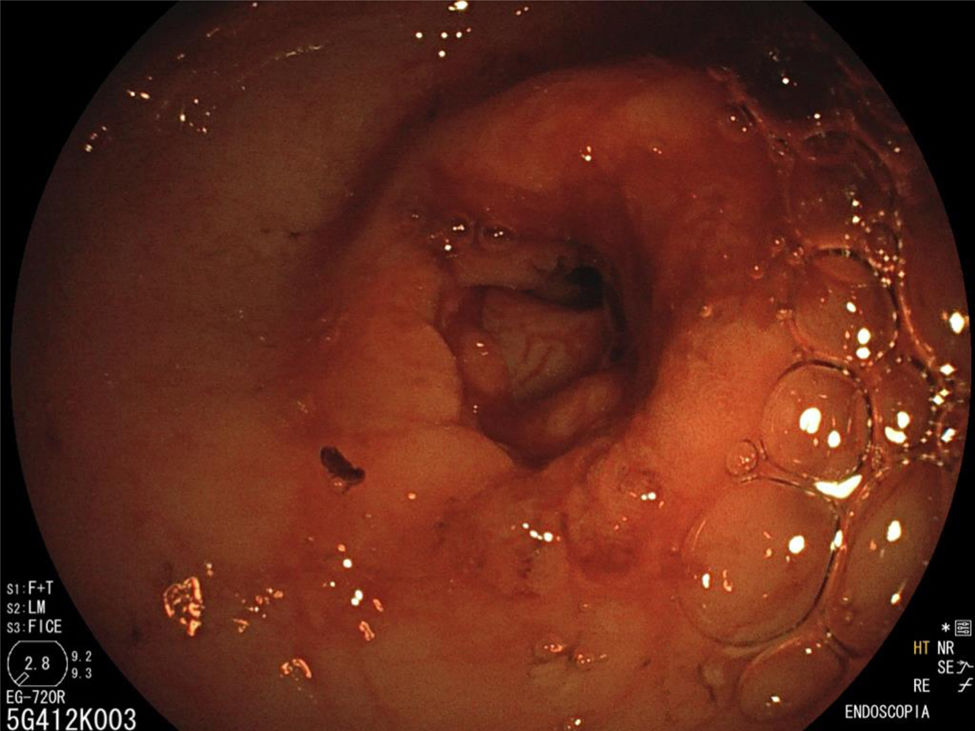

La endoscopia reveló un estrechamiento del píloro que impedía el paso del endoscopio al duodeno (fig. 1), por lo que se realizó dilatación hidroneumática con balón (figs. 2 y 3). Las biopsias informaron gastritis asociada a Helicobacter pylori e hiperplasia foveolar.